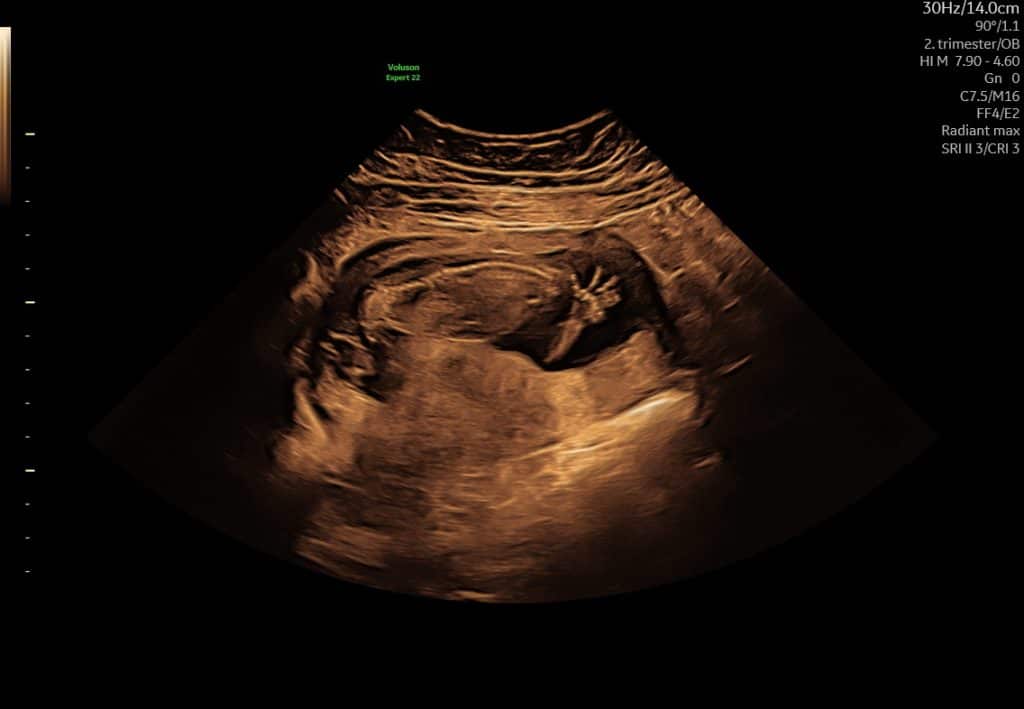

Ultralyd i uge 18–21

I denne periode udføres den store gennemgang af barnets anatomi i det offentlige. Ved ultralyd kan man typisk se:

- organer og kropsdele mere detaljeret

- rygrad, mave, blære og ekstremiteter

- barnets generelle trivsel

Fosteret fylder nu mere på skærmen, og det er ofte muligt at få meget klare billeder.

Ultralyd uge 18 ansigt i profil

Ultralyd i uge 18 som viser barnets rygsøjle set i længdesnit

Ultralyd i sen graviditet. Det er normalt, at man kun ser dele af barnet ad gangen.